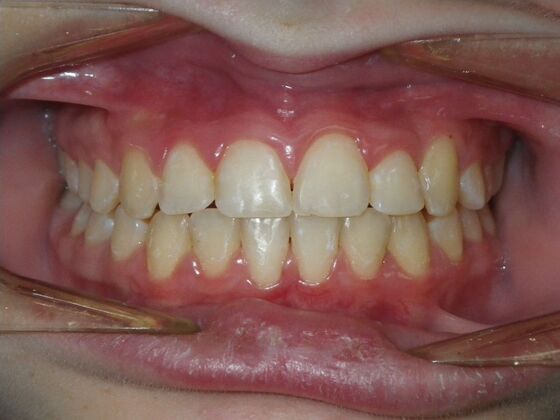

Orthodontics: Case 43

Patient presented with mixed dentition and mild deep overbite, excessive overjet,and rotated lower incisors. She also had a lower bilateral lingual retainer, preventing lower molars from coming forward. She was treated with utility archwires initially, waiting for eruption of cuspids and bicuspids. This was followed by conventional straight wire appliances and upper and lower standard hawley retainers.